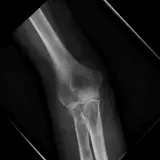

PACS์—์„œ ๊ธฐ๋Œ€ํ•  ์ˆ˜ ์žˆ๋Š” ๋ชจ๋“  ๋„๊ตฌ๋ฅผ ๊ฐ–์ถ˜ ์™„์ „ํ•œ ์ธํ„ฐ๋ž™ํ‹ฐ๋ธŒ ์ฆ๋ก€ — ์Šคํฌ๋กค, ์œˆ๋„์šฐ ์กฐ์ ˆ, ํ™•๋Œ€/์ถ•์†Œ, ํŒจ๋‹, ๊ณ„์ธก, ROI, ์ „์ฒด ํ™”๋ฉด ๋ชจ๋“œ๊นŒ์ง€ ์ง€์›ํ•ฉ๋‹ˆ๋‹ค.

์ฃผ์š” ์†Œ๊ฒฌ์„ ์ฆ๋ก€์— ์ง์ ‘ ํ‘œ์‹œํ•˜๋Š” ํ’๋ถ€ํ•œ ์ฃผ์„์ด ํฌํ•จ๋˜์–ด ์žˆ์Šต๋‹ˆ๋‹ค. ์ฆ๋ก€ ์„ค๋ช…์˜ ์—ฐ๊ฒฐ๋œ ์†Œ๊ฒฌ์„ ํด๋ฆญํ•˜๋ฉด ์Šค์บ” ๋‚ด ์ •ํ™•ํ•œ ์œ„์น˜๋กœ ๋ฐ”๋กœ ์ด๋™ํ•ฉ๋‹ˆ๋‹ค.